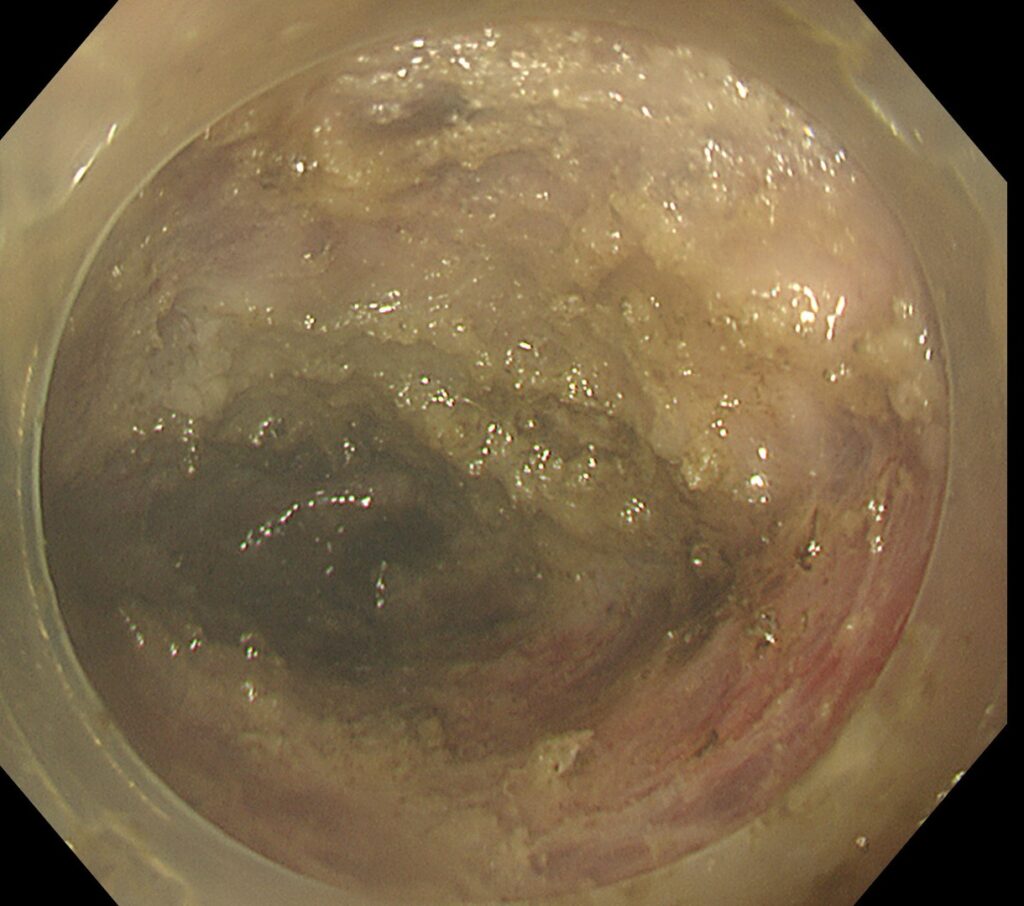

NBI拡大で、大腸癌であることを確認。

下が筋層、上が腫瘍です。遠位側の切開部位まで開通したら、両側を電気メスで外してあげると・・・